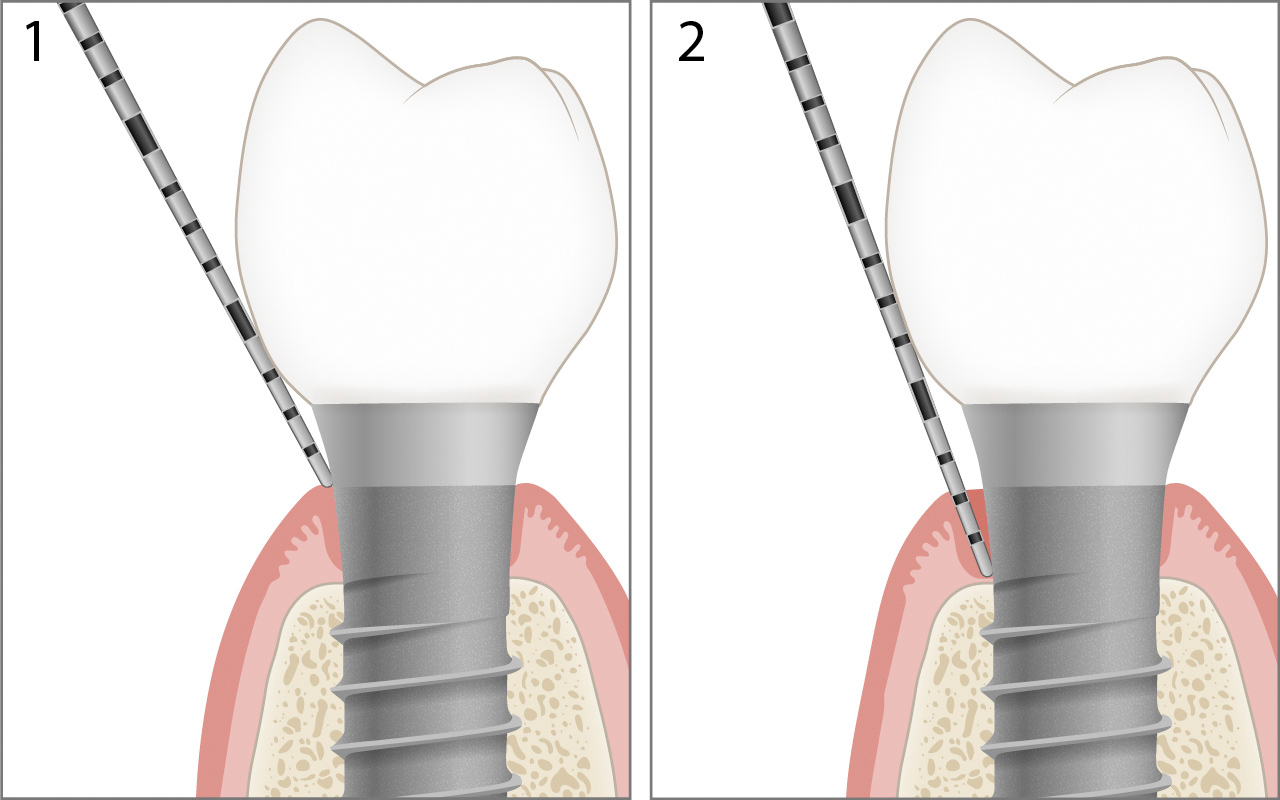

Periimplantäre Tasche

Im periimplantär erkrankten Gewebe mit Alveolarknochenverlust kann der Rand der Suprakonstruktion etwas unterhalb oder überhalb der periimplantären Mukosa liegen. Die Distanz vom Rand der periimplantären Mukosa zum Boden der periimplantären Tasche wird als Sondierungstiefe 2 festgehalten.

Die Berechnung des Alveolarknochenniveaus (Attachmentniveau) in der oben gezeigten Abbildung lautet:

Alveolarknochenniveau 6mm = Sondierungstiefe 7mm – Margo Mucosae (Gingivae) 1mm